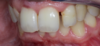

Cas clinique 4 : pose de facettes céramiques sur les incisives latérales

Anomalie de proportion des dents

Anomalie de proportion des dents. Cas clinique 4 : pose de facettes céramiques sur les incisives latérales pour l'esthétique.